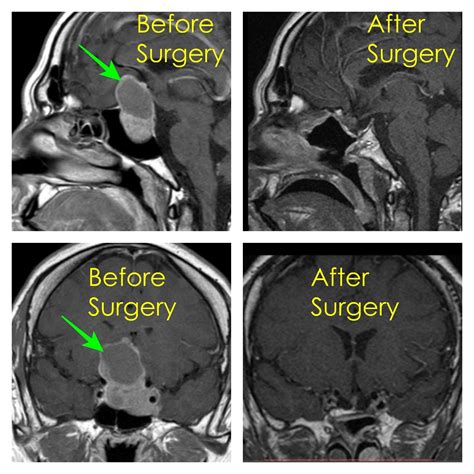

• Imaging Tests: MRI or CT scans to provide detailed images of the pituitary gland and surrounding structures.

• Tumor Removal: The tumor is carefully removed using specialized instruments. The surgeon takes care to preserve the normal pituitary tissue and surrounding structures.

Long-Term Outcomes

The long-term outcomes of pituitary gland surgery are generally positive, with many patients experiencing significant improvements in their symptoms and quality of life. However, the specific outcomes can vary depending on several factors, including:

• The size and type of the tumor

• The surgical approach used

• The patient’s overall health and response to treatment